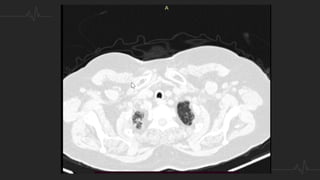

TÉCNICA - ANGIOTAC

• Contraste: 50 ml a un flujo de 4 ml/sg y lavado posterior con 30 ml de

suero salino

• Kilovoltaje se decide en función del peso del paciente: 80 kV hasta 70

Kg, 100 kV entre 70-100 Kg y 120 kV por encima de 100 Kg.

• Se dispara con un retardo de 6 seg, con técnica de bolus tracking,

posicionando el (ROI) en la arteria pulmonar, a 100 (UH).

• Adquisición se realiza con la respiración suspendida, pero no tras

inspiración profunda para evitar la dilución del contraste en la aurícula

derecha.

TÉCNICA - ANGIOTAC •Contraste: 50 ml a un flujo de 4 ml/sg y lavado posterior con 30 ml de suero salino • Kilovoltaje se decide en función del peso del paciente: 80 kV hasta 70 Kg, 100 kV entre 70-100 Kg y 120 kV por encima de 100 Kg. • Se dispara con un retardo de 6 seg, con técnica de bolus tracking, posicionando el (ROI) en la arteria pulmonar, a 100 (UH). • Adquisición se realiza con la respiración suspendida, pero no tras inspiración profunda para evitar la dilución del contraste en la aurícula derecha.